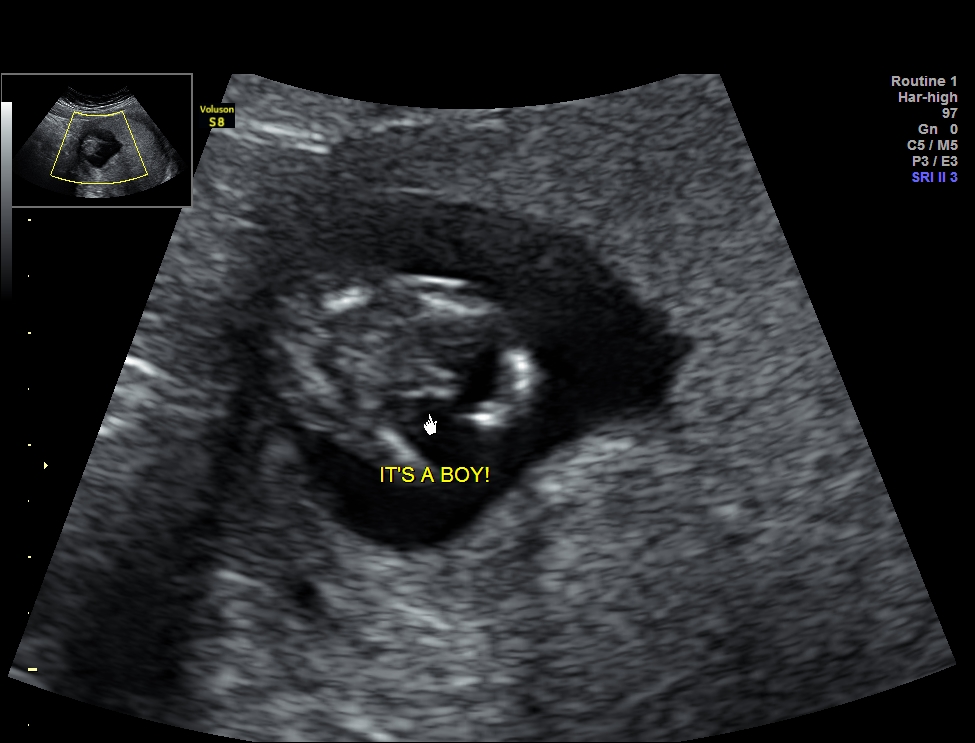

Is this definitely a boy?

Ultrasound is from exactly 13 weeks.

U/S tech said 100% boy.

No nub shot. Just potty shot.

I know genitals looks same in boy and girl at 11 weeks. But so far I have not seen any 13 week potty shots that look like mine and ended up being a girl.

I also heard they are more likely to Guess right with boy guesses than girl guesses at 13 weeks.

I won't say what I'm hoping for because I don't want people to tell me what they think I want to hear. I just want the truth. Is this a boy?

If there's a chance it's not, I would love to see a similar 13 week potty shot that ended up being a girl. Because I have not been able to find one anywhere.

Attachment 35033